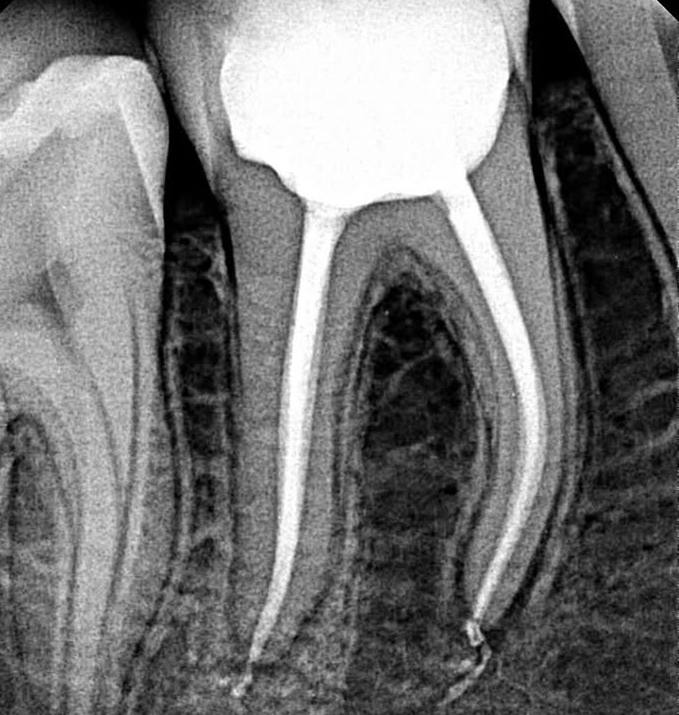

5. What Condition can be seen in this X ray regarding the tooth # 4.6?